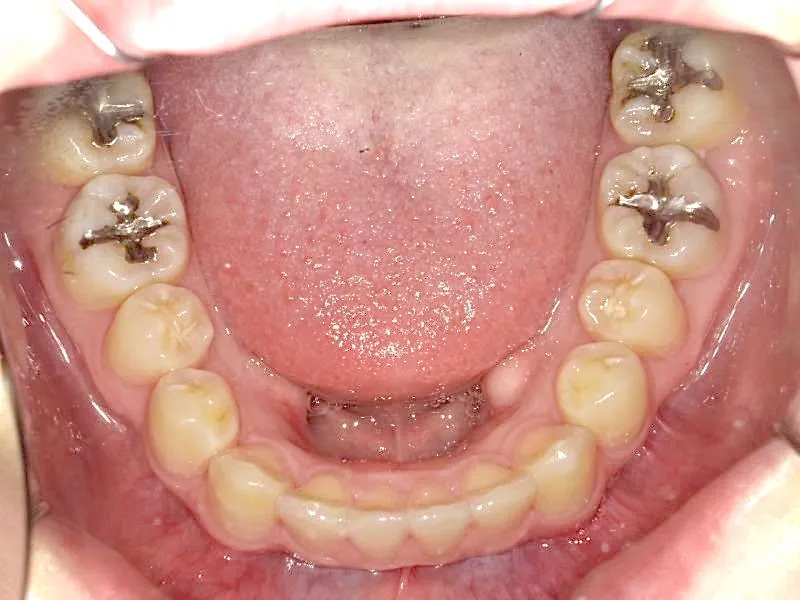

• 初診時

初診時

奥歯が内側と前方にかたむき上下の歯がガタガタに生えています。

90度ねじれた歯もあります。前歯も出っ歯になっています。

歯は抜かず、歯科矯正用アンカースクリューを用いて治療しました。